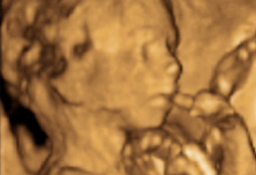

Ecografía de la semana 20 o morfológica, así se denomina esta prueba diagnóstica, considerada como la primera "foto" del bebé. Decimos esto porque el ecografista recorre con mucha calma y cautela todas las estructuras básicas y órganos del bebé, que a esta edad gestacional se suelen ver con claridad. El pequeño aún se mueve con soltura dentro del líquido amniótico, a veces esquivando la mirada del ecografista, algo que en pocas semanas hará con mucha más dificultad. Merece la pena ver esta galería de ecografías de la semana 20 (y alrededores, puesto que se puede hacer a partir de las semana 18) en 2D, 3D y 4D. En la eco de la semana 20 también pueden detectarse algunas malformaciones fetales, pero lo usual que que se compruebe la buena salud del feto.